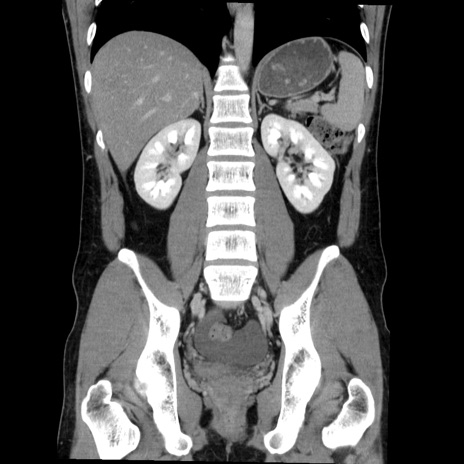

症例36(冠状断像)

【症例】20歳代 男性

【主訴】心窩部痛

【現病歴】今朝より上腹部痛あり。一旦軽快していたが再度出現したため救急要請。昨日夕に白身の魚を含む刺身を食べた。

【身体所見】BP 136/89mmHg、HR 74/min、BT 37.0℃、腹部:膨満、軟、心窩部に圧痛あり。反跳痛なし、筋性防御なし、腸雑音やや亢進あり。

【データ】WBC 17700、CRP 0.48